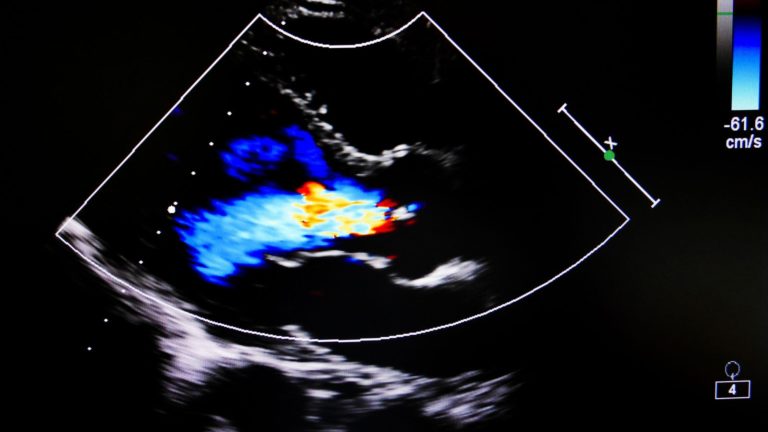

Imagen Doppler en Color: Con este modo de imagen, los usuarios pueden visualizar y analizar el flujo sanguíneo, su dirección y vascularización. La imagen Doppler en color se usa a menudo en cardiología para ayudar a analizar las condiciones cardíacas.

- Cardiología: La ecocardiografía puede evaluar el funcionamiento general del corazón. Las máquinas de ultrasonido pueden indicar el volumen y el flujo de sangre a través de las cámaras. La ecocardiografía Doppler se realiza comúnmente para detectar problemas con las válvulas del corazón.